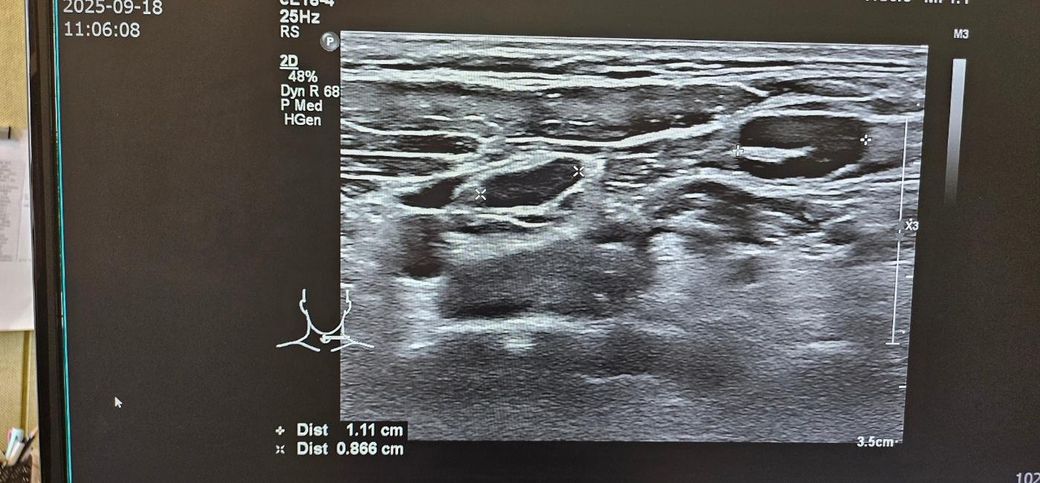

경부초음파 자세하게 설명좀 부탁드립니다

통증이있어서 초음파했는데

약먹고 통증은 없습니다

초음파 보시고 자세히 설명좀 부탁드립니다..

• 1번 째 사진